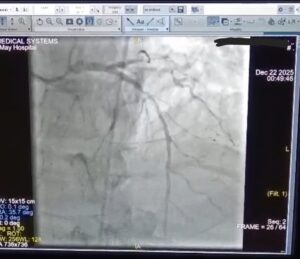

تم على الفور بقسم الطواريء بدأ الانعاش القلبي الرئوي وتركيب انبوبة حنجرية حتى تم استعادة النبض وسرعان ما تم تفعيل بروتوكول القسطرة القلبية الطارئة وتم نقل المريض إلى وحدة القسطرة القلبية وتم إجراء قسطرة لفتح الشريان الرئيسي وتركيب دعامتين دوائيتين.